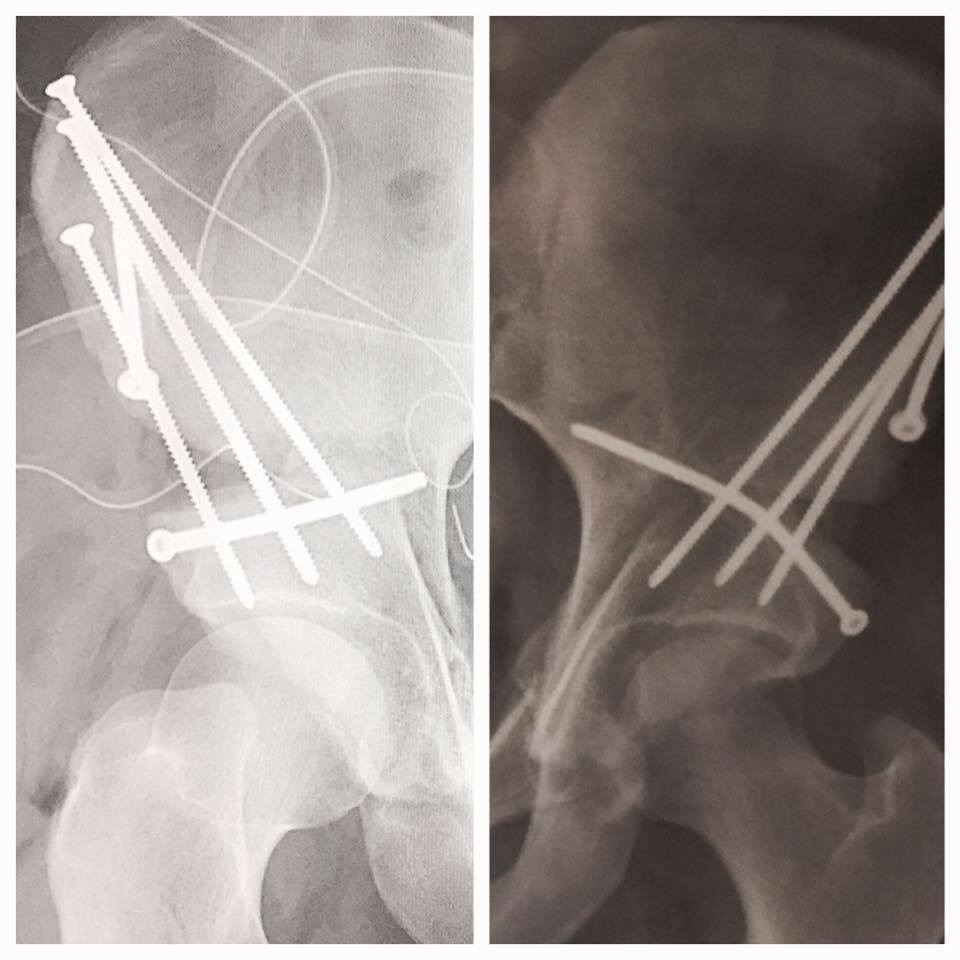

In November of 2015, I had my first appointment with Dr. Buly. I remember being so nervous upon my arrival; however, the minute I stepped into his office and met his nurse, Elaine, I was at ease. After reviewing my scans, Dr. Buly spent one full hour with me talking about my lifestyle, what I liked to do, what sports I played, etc. To our surprise, he diagnosed me with bilateral hip dysplasia. He wrote all over my x-rays and explained the condition and treatment in the most calm, warm, and compassionate way. He informed us how he was going to be joined by surgeon Dr. David Helfet for the PAO surgery. I had so much faith in Dr. Buly that I scheduled my first PAO at that first appointment! The morning of my PAO surgery, May 26, 2016, Dr. Buly came in, held my hand, and told me that I was going to be okay. I went into the OR smiling! After that first surgery, I had my screws removed the following March of 2017 and my RPAO that May of 2017.